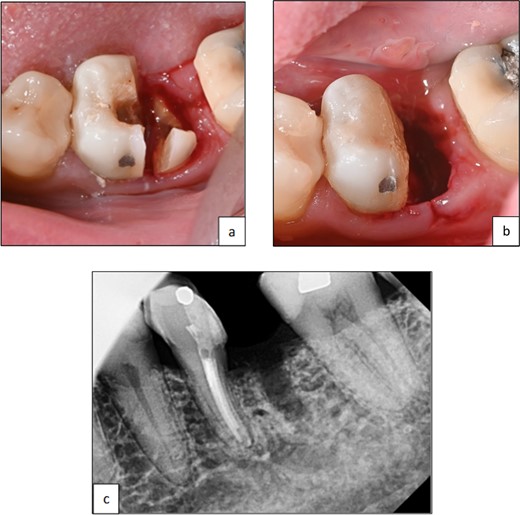

Following root canal treatment, hemisection and removal of the distal root were performed under local anesthesia. The furcation area was marked on the crown to guide tooth sectioning. Using a low-speed surgical fissure bur under normal saline irrigation, a vertical cut was made to separate the tooth. The distal root was elevated and removed in one piece using a periosteal elevator. Sharp edges and margins were smoothened, and the coronal tooth structure was restored. Hemostasis was achieved using a pressure pack.

The patient was monitored for one year with no reported symptoms. Due to extensive filling and secondary caries in the adjacent left second mandibular molar (tooth 37), both the mesial root of tooth 36 and tooth 37 were prepared for a zirconia bridge. Tooth 36 received a full-coverage crown, while tooth 37 was restored with an onlay. Tooth 36 was anatomically restored to conform esthetically and functionally with the existing occlusion (Fig. 4 and 5).

Clinical photographs showing (a) line of resection through furcation area and separation of mesial and distal roots, (b) after elevation of root and smoothening of sharp edges, (c) periapical radiograph of tooth 36 after hemisection and removal of distal root.